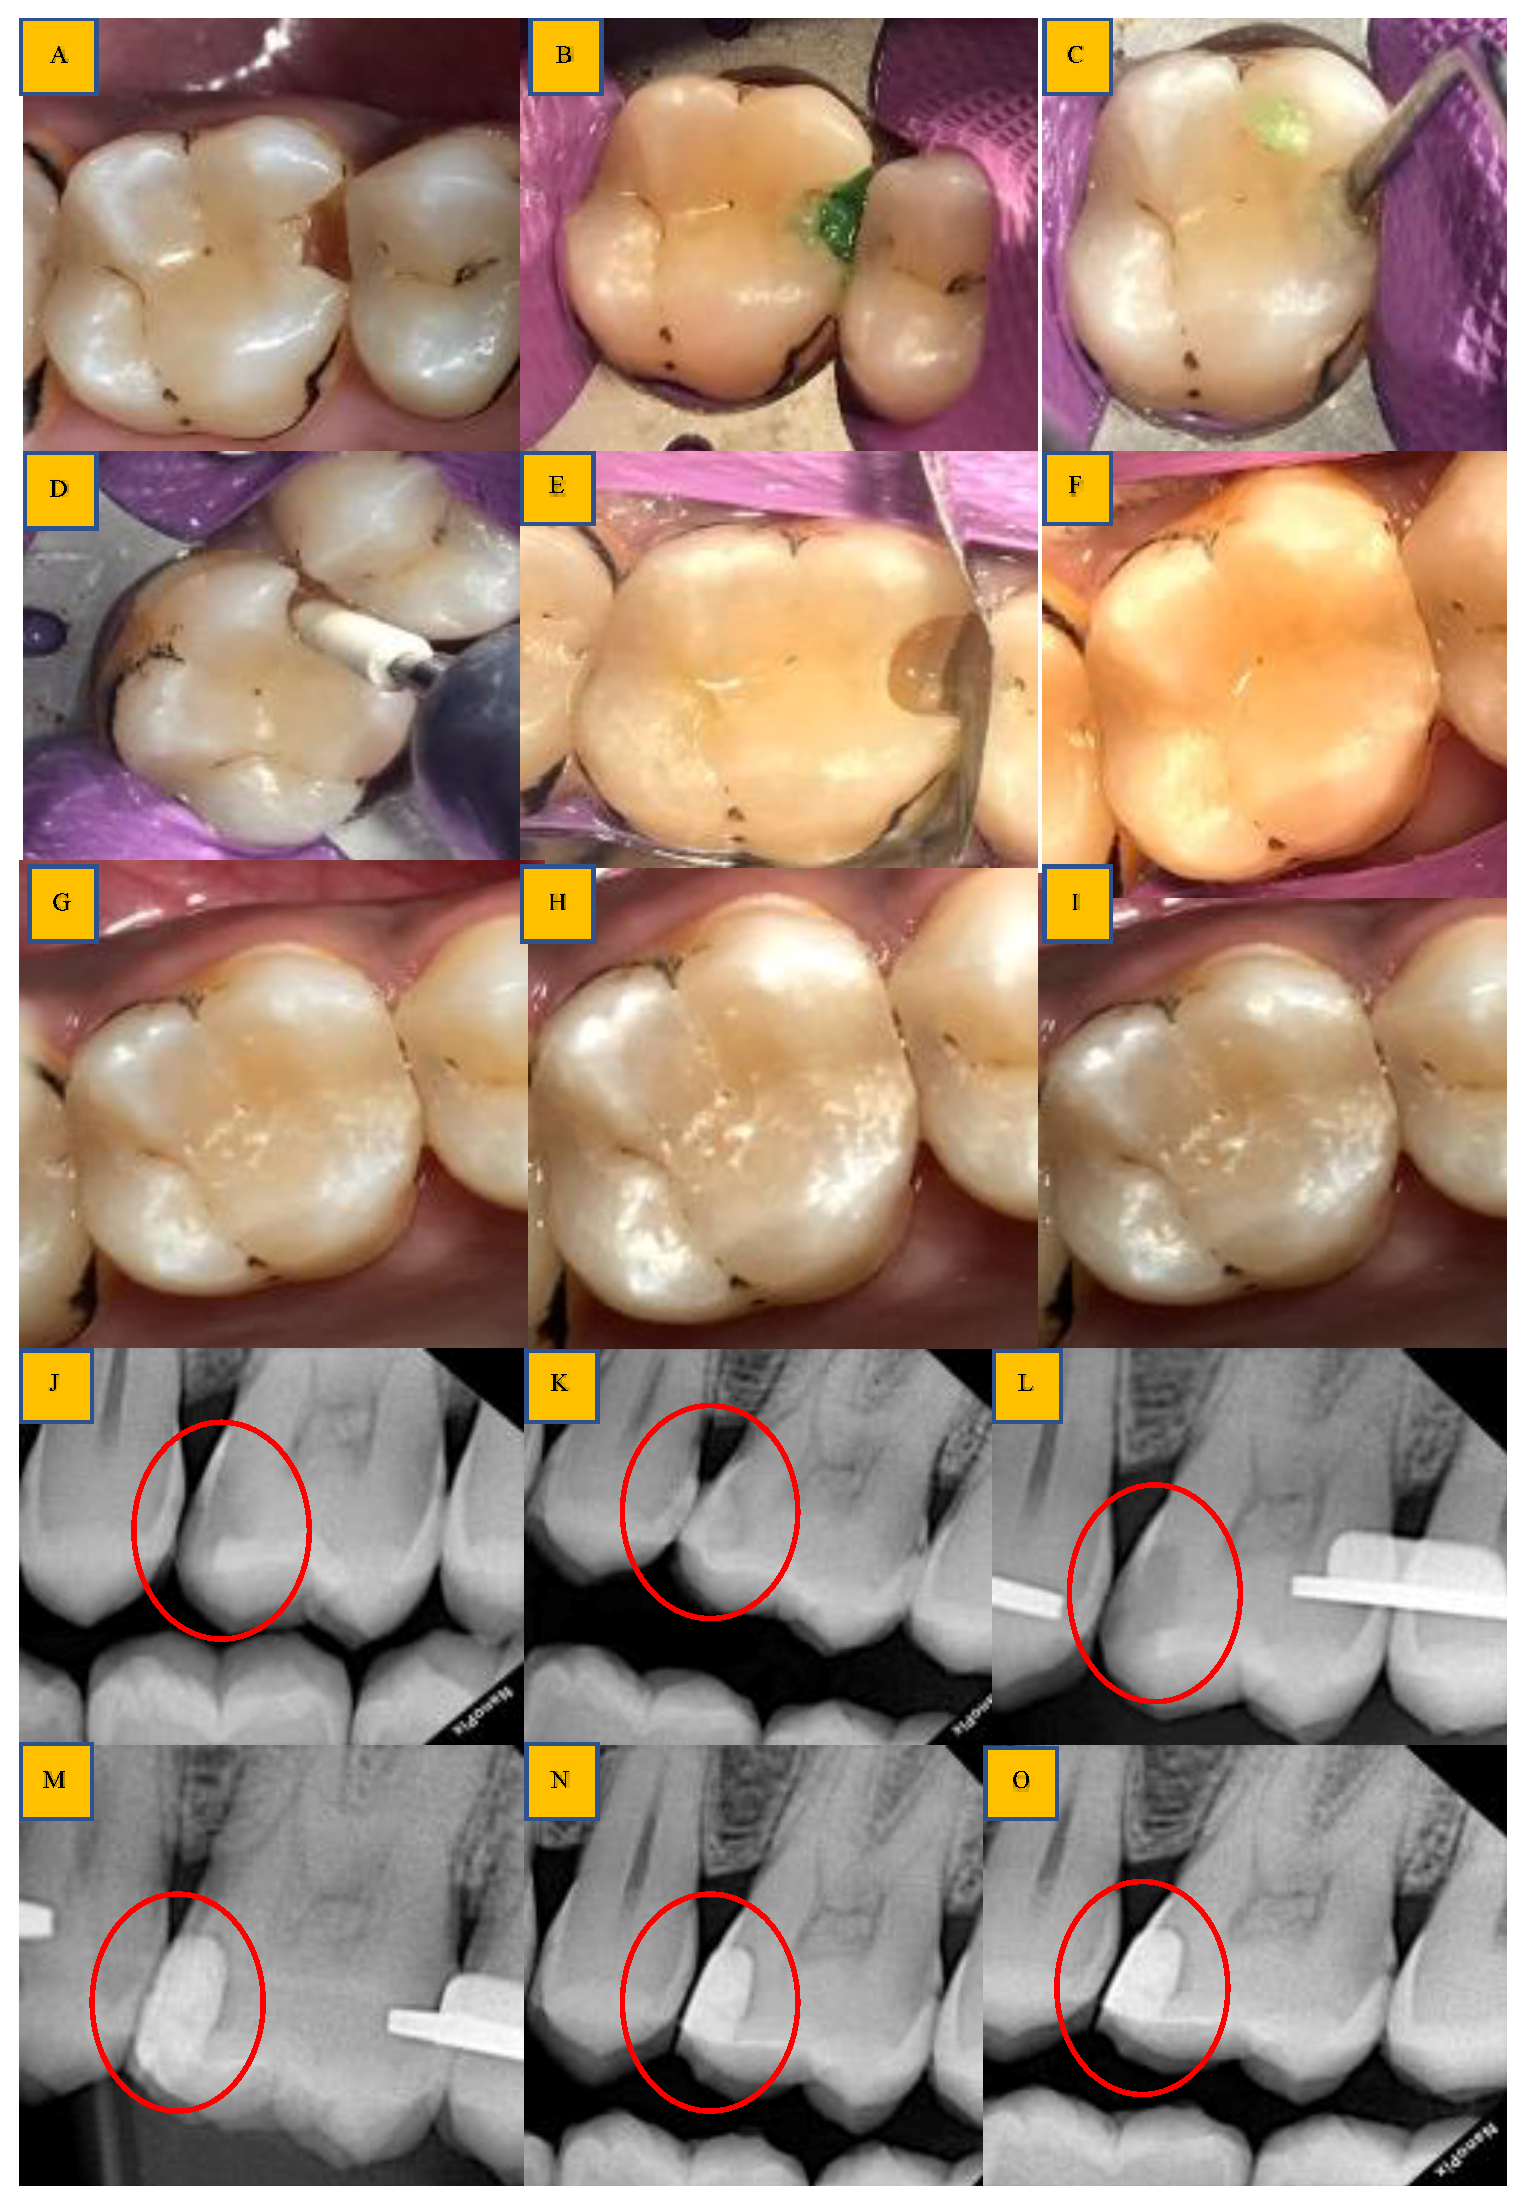

2.4. Treatment

Caries Excavation and Treatment Time